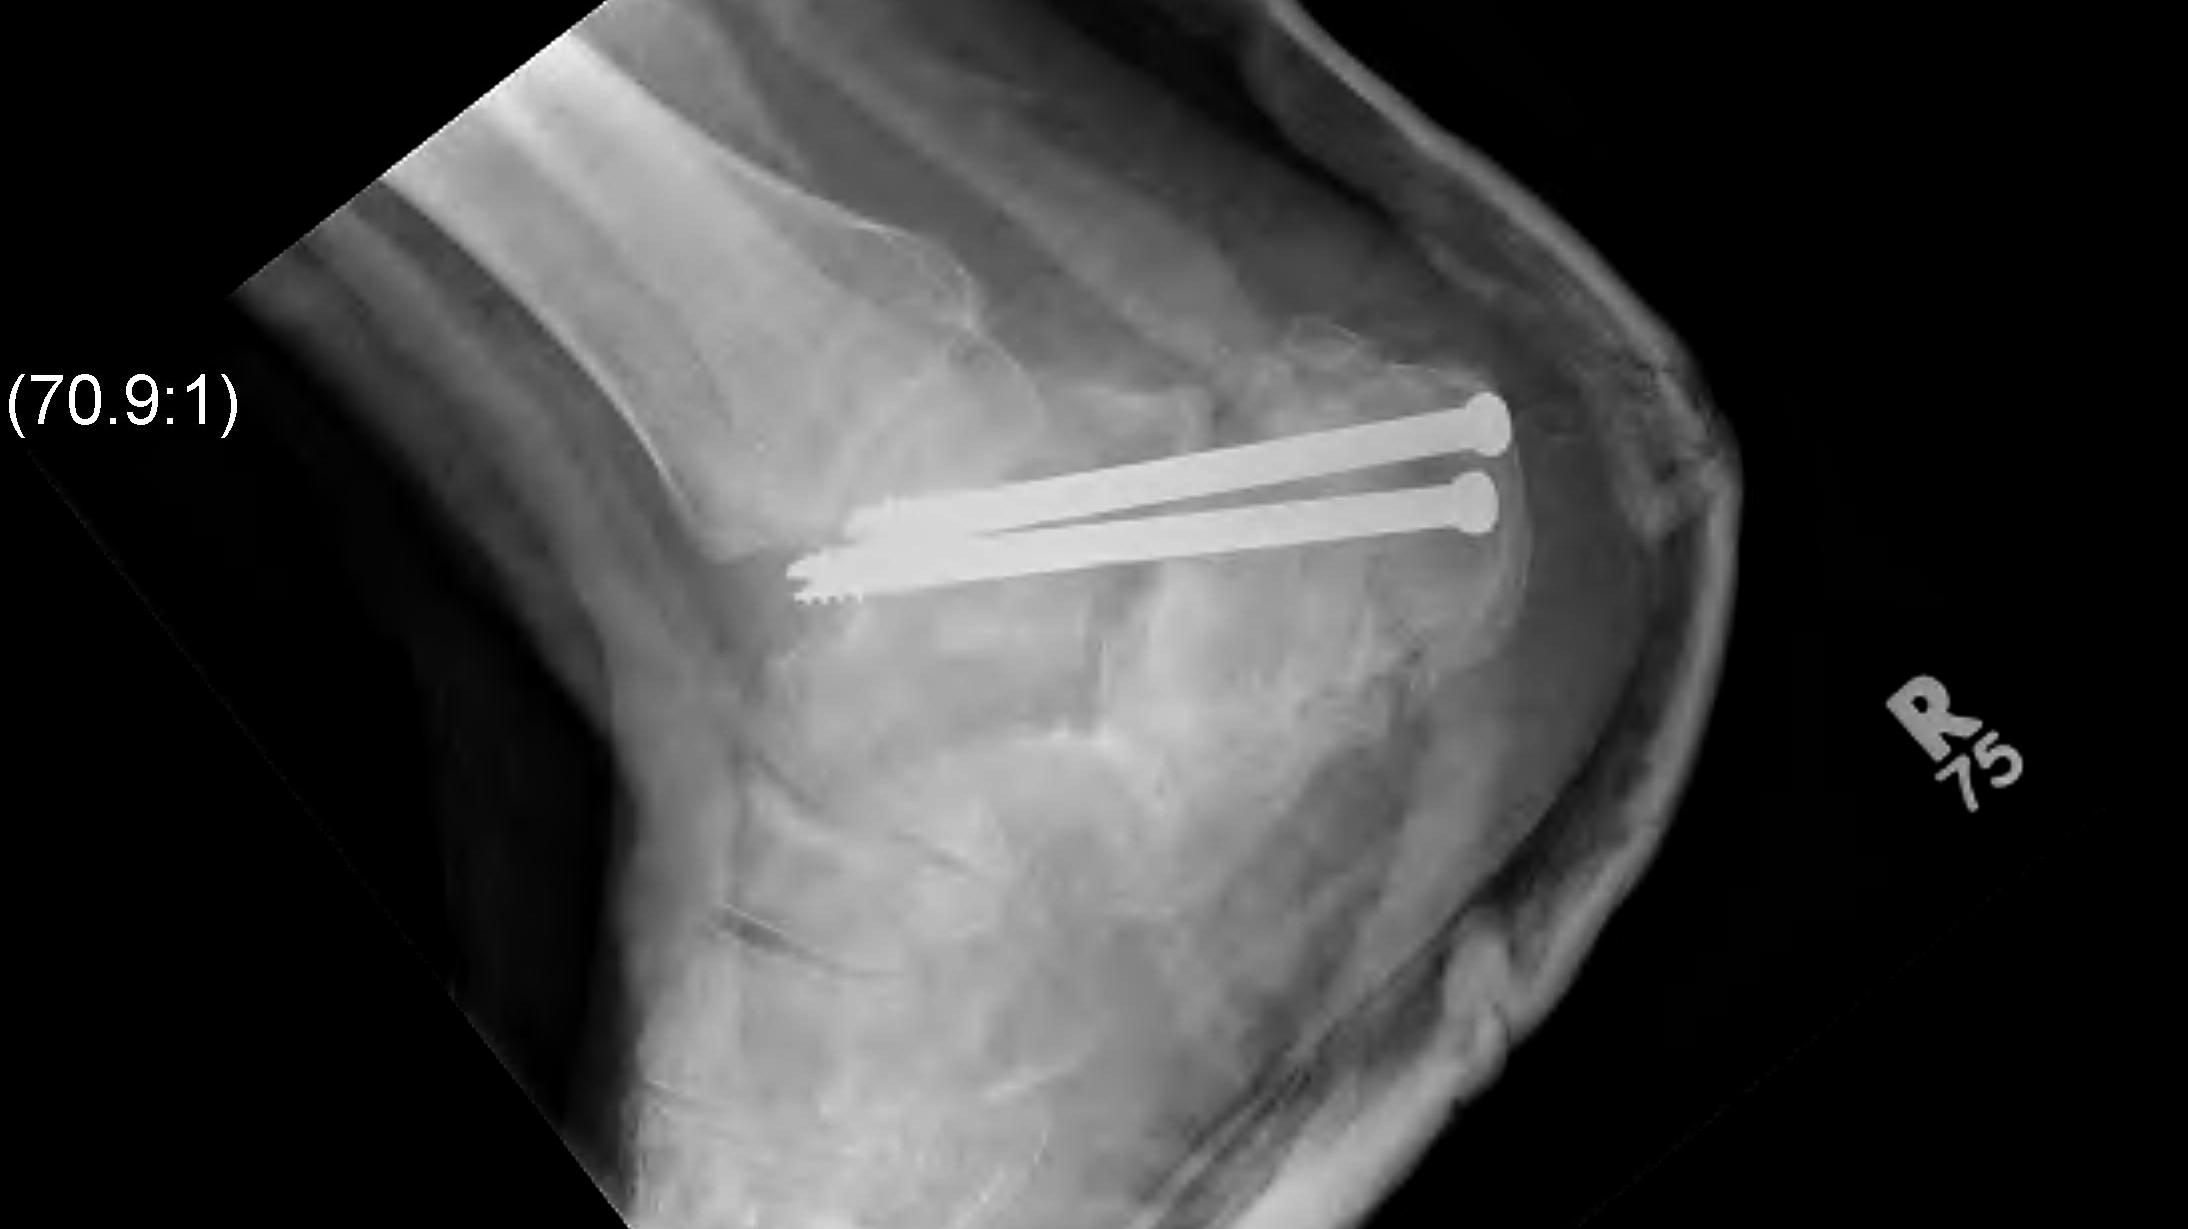

Percutaneous fixation versus MIS / sinus tarsi

Feng et al BMC Musculoskeletal Disorders 2016

- RCT of 80 patients

- percutaneous screws v sinus tarsi approach / plate

- comparable clinical outcomes

- better restoration of heel width with sinus tarsi approach